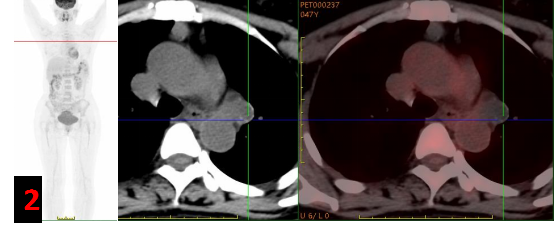

PET/CT?

主動脈弓左旁不規則混雜密度腫塊影,邊緣見斑點狀/環形鈣化灶,FDG代謝不高(SUVmax約0.3-1),考慮良性病變(圖2)。

PET/CT能夠從代謝的角度提供更有價值的診斷信息,支氣管源性囊腫往往呈低代謝或代謝缺損表現;同時PET/CT是全身檢查,對于臨床高度懷疑惡性腫瘤的患者能夠提供更全面的信息,提高診斷準確度。

本例患者由于增強CT表現不典型,臨床為排除惡性腫瘤轉移選擇PET/CT進一步明確診斷。PET/CT展示病灶無代謝,給出了良性病變的定性診斷,最終得到病理證實。